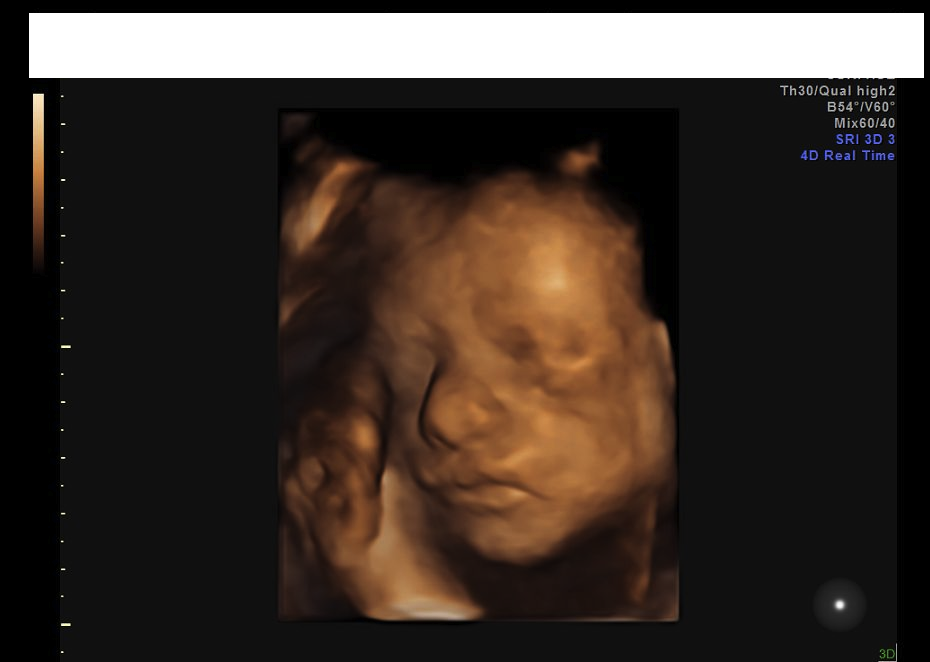

27 Week 4d Ultrasounds Please Post May 2016 Babies Forums